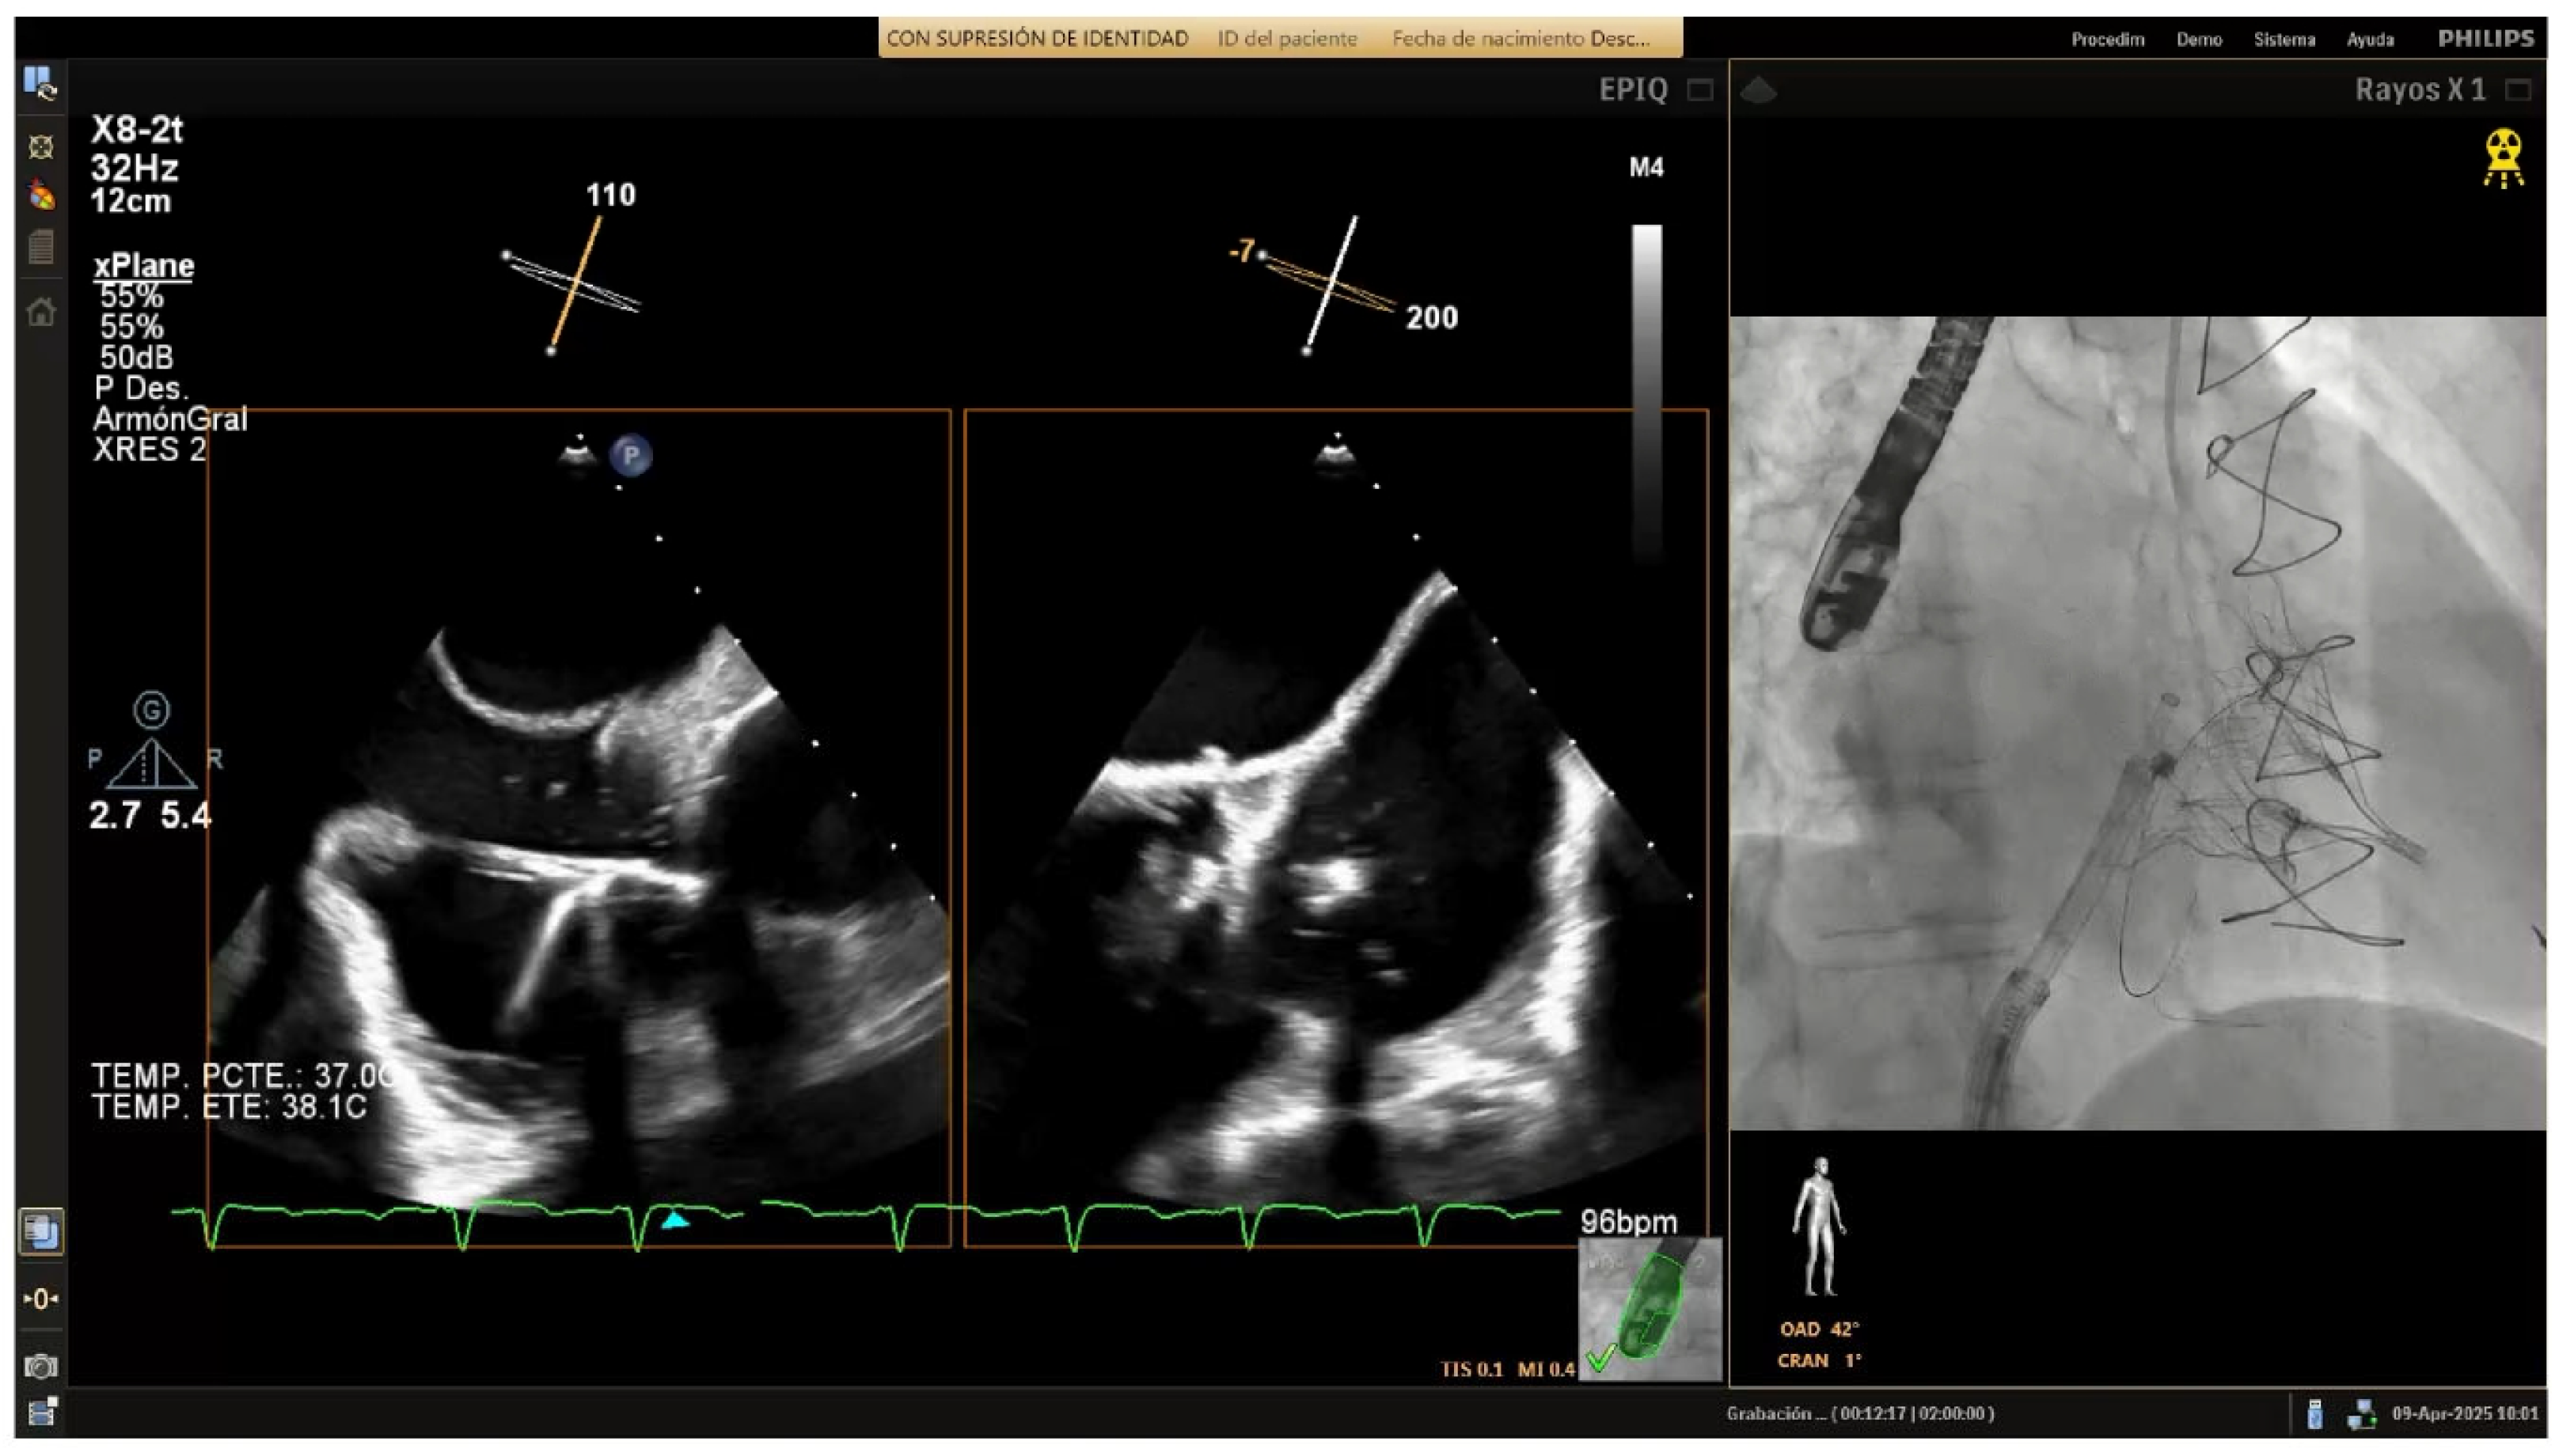

As the guide catheter approaches the tricuspid valve (

Figure 4), it is important to avoid structural interference or leaflet damage. Angiographically, the left anterior oblique projection helps visualize the anteroseptal commissure of the tricuspid annulus and ensures avoidance of the RCA course. Echocardiographically, transgastric views help visualize the anterior and posterior annulus, while high, mid, and deep esophageal views are useful for assessing the lateral annulus.

After the catheter is near the anteroseptal commissure, TEE and angiographic views are used together to check the IC tip alignment as it moves towards the tricuspid annulus. RAO projections allow visualization of the IC’s approach to the annulus with respect to its surrounding anatomy in order to confirm that the catheter’s tip follows the intended trajectory towards the target anchor points and is not obstructed by the leaflet or at risk of inducing injury. TEE bi-plane views are then employed to monitor precise positioning in relation to the hinge points and to ensure that the IC makes accurate contact with the annular tissue.

Figure 4.

Delivery system navigation. The mid-esophageal bicaval view supports real-time visualization of the steerable sheath and guide catheter, while the mid-esophageal short-axis view aids in assessing the distance to the aorta. As the guide catheter nears the tricuspid valve, fluoroscopic left anterior oblique projection helps identifying the anteroseptal commissure and avoiding the right coronary artery.